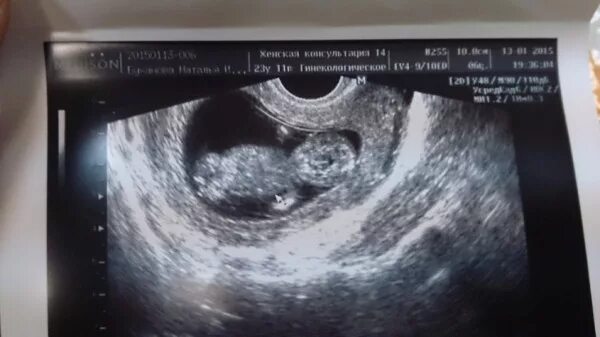

12 недель и два дня